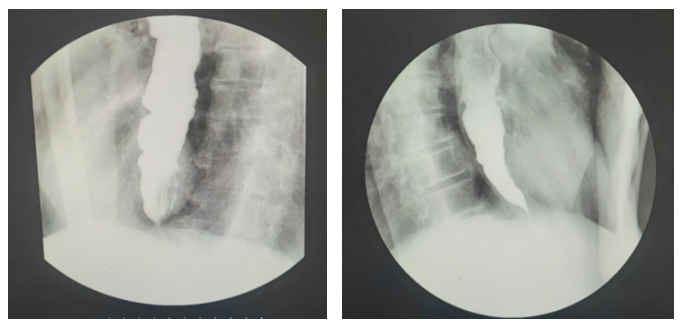

上消化道造影提示:食管中下段扩展,贲门呈“鸟嘴样”改变。